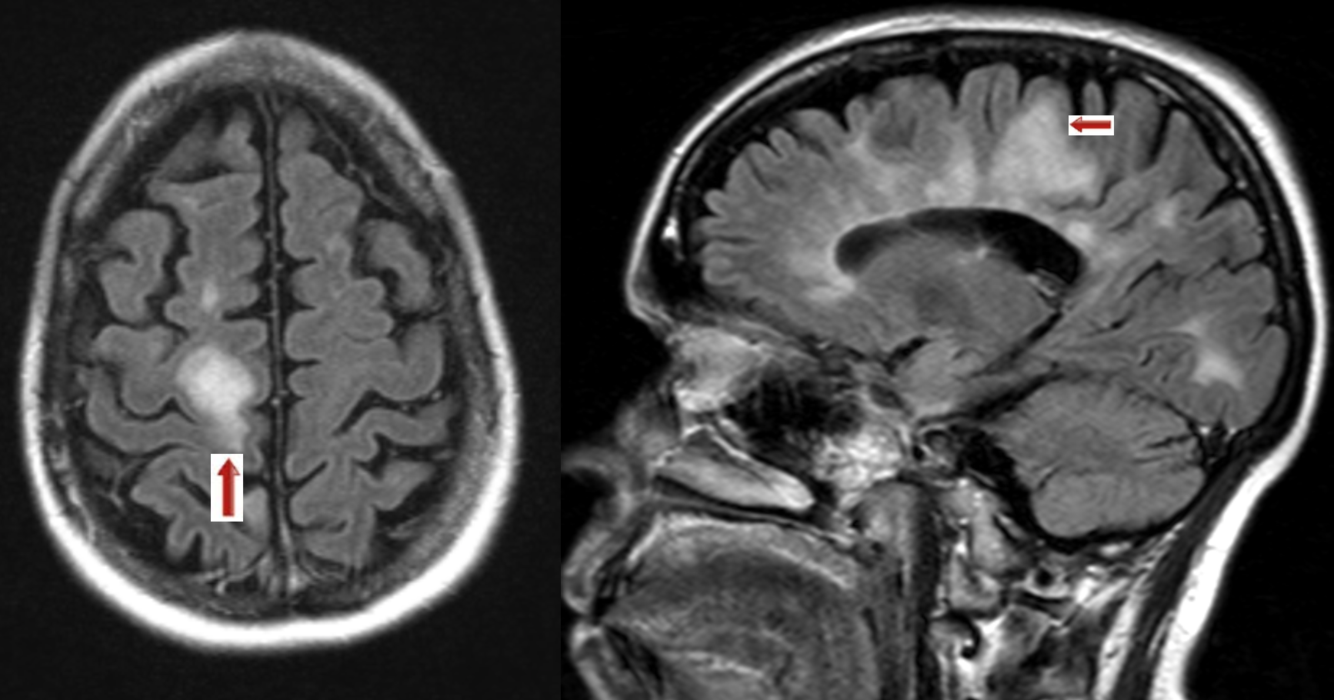

A 30 year-old female presented with with double vision.

Multiple sclerosis - Juxtacortical lesions